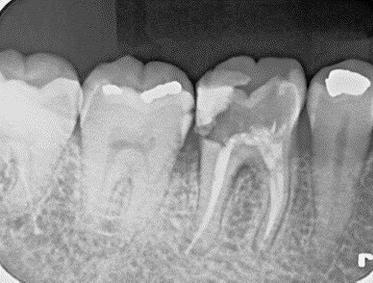

Before術前

After術後